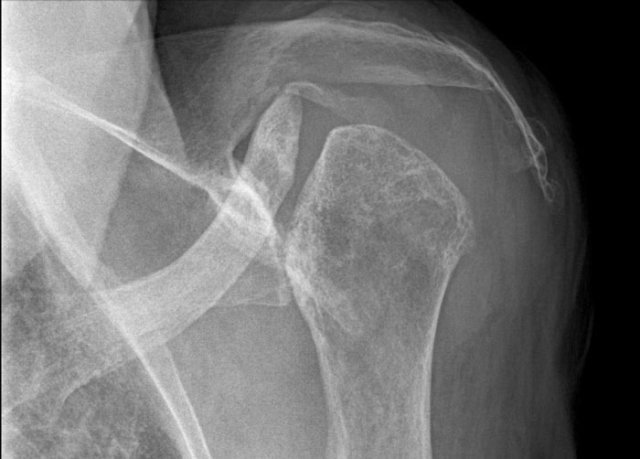

Hatchet lesion. Ankylosing spondylitis of the humeral head Hatchet lesion. Ankylosing spondylitis of the humeral head

The Hatchet sign is a circumscribed erosion of the lateral-dorsal aspect of the humeral head leading to a hatchet-shaped deformity.

A hatchet is a small axe.

This deformity is typical for ankylosing spondylarthritis.

Avascular necrosis of the humeral head Avascular necrosis of the humeral head

Hatchet sign versus avascular necrosis

The hatchet sign differs from the deformity seen in avascular necrosis, where there is progressive collapse of the articular surface of the humeral head.

Milwaukee shoulder syndrome Milwaukee shoulder syndrome

Milwaukee shoulder

A rare shoulder arthropathy that can simulate the hatchet shoulder is the Milwaukee shoulder syndrome.

It is characterized by rupture of the rotator cuff and large joint and bursal effusions with deposition of hydroxyapatite crystals leading to rapid destruction of the glenohumeral joint.

Image

Severe destruction of the humeral head with cephalic migration and erosions of the acromion indicating total cuff rupture.

In the Milwaukee shoulder syndrome, symptoms are often much milder than imaging suggests.

In this case, there was no attempt to diagnose calcium hydroxyapatite crystals in the synovium.

Based on clinical and radiographic findings, Milwaukee shoulder syndrome was diagnosed.